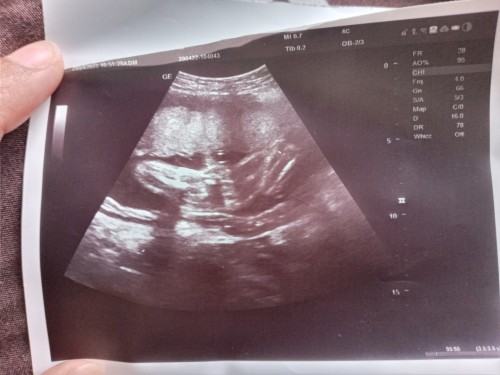

น้องเพศอะไร?

แม่ๆช่วยดูหน่อยค่ะ น้องเป็นผู้หญิงหรือผู้ชาย มองไม่ออกจริงๆ 🙏🥰